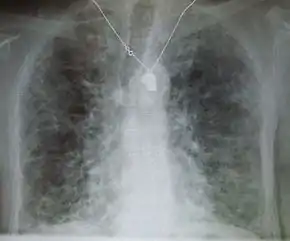

Lung

Side effects of oral amiodarone at doses of 400 mg or higher include various pulmonary effects.[27] The most serious reaction is interstitial lung disease. Risk factors include high cumulative dose, more than 400 milligrams per day, duration over two months, increased age, and preexisting pulmonary disease. Some individuals were noted to develop pulmonary fibrosis after a week of treatment, while others did not develop it after years of continuous use.[27] Common practice is to avoid the agent if possible in individuals with decreased lung function.

The most specific test of pulmonary toxicity due to amiodarone is a dramatically decreased DLCO noted on pulmonary function testing.